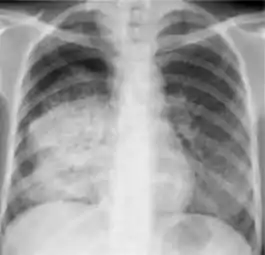

In active pulmonary TB, infiltrates or consolidations and/or cavities are often seen in the upper lungs with or without mediastinal or hilar lymphadenopathy.[1] However, lesions may appear anywhere in the lungs. In HIV and other immunosuppressed persons, any abnormality may indicate TB or the chest X-ray may even appear entirely normal.[1]

Old healed tuberculosis usually presents as pulmonary nodules in the hilar area or upper lobes, with or without fibrotic scars and volume loss.[1] Bronchiectasis and pleural scarring may be present.

Abnormalities on chest radiographs may be suggestive of, but are never diagnostic of, TB.[1] However, if a person has a positive response to the tuberculin skin test and no symptoms of the disease, chest radiographs can be used to rule out the possibility of pulmonary TB.